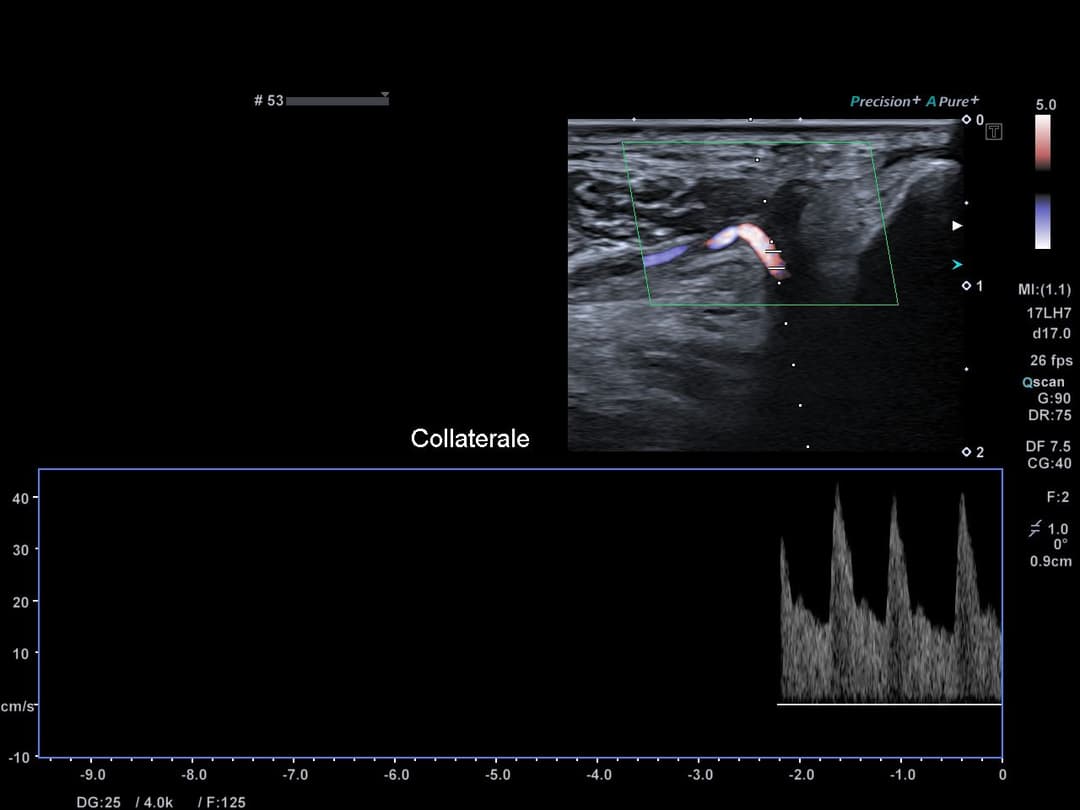

Reperméabilisation de l'artère radiale en distalité de la tabatière anatomique par une branche profonde de l'artère ulnaire, venant de l'arcade palmaire dorsale (profonde). L'arcade palmaire superficielle n'étant pas complète chez cette patiente.

Hyperdébit compensateur de cette branche collatérale venant du réseau ulnaire